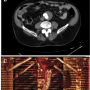

A 75-year-old man, with ongoing smoking habit and arterial hypertension, was admitted to our institution for percutaneous exclusion of an abdominal aortic aneurysm incidentally discovered by his family practitioner following a computed tomography (CT) scan of the abdomen and pelvis for lumbar vertebral disc herniation. The CT scan disclosed a fusiform AAA measuring 6.2 x 5.1 cm originating below the renal arteries and extending to the level of the aortic carrefour. A limited amount of thrombus was present at the level of the AAA without involvement of the proximal landing zone, which measured 0.7 cm in length. CT scan examination demonstrated suitability for EVAR, and the correct EVG type was chosen based upon size and length.

The procedure was then completed by deploying a 20 x 14 cm contralateral leg during inflation of a 34 mm tri-lobated balloon (W. L. Gore) in the EVG body at the level of the proximal stent edge, to stabilize the graft during contralateral sheet gate insertion, with a satisfactory final result (Figure 5). The patient was discharged two days after the procedure, and blood draws did not disclose any evidence of renal damage. Computed tomography demonstrated complete AAA exclusion without any endoleak at up to 6 months follow-up.